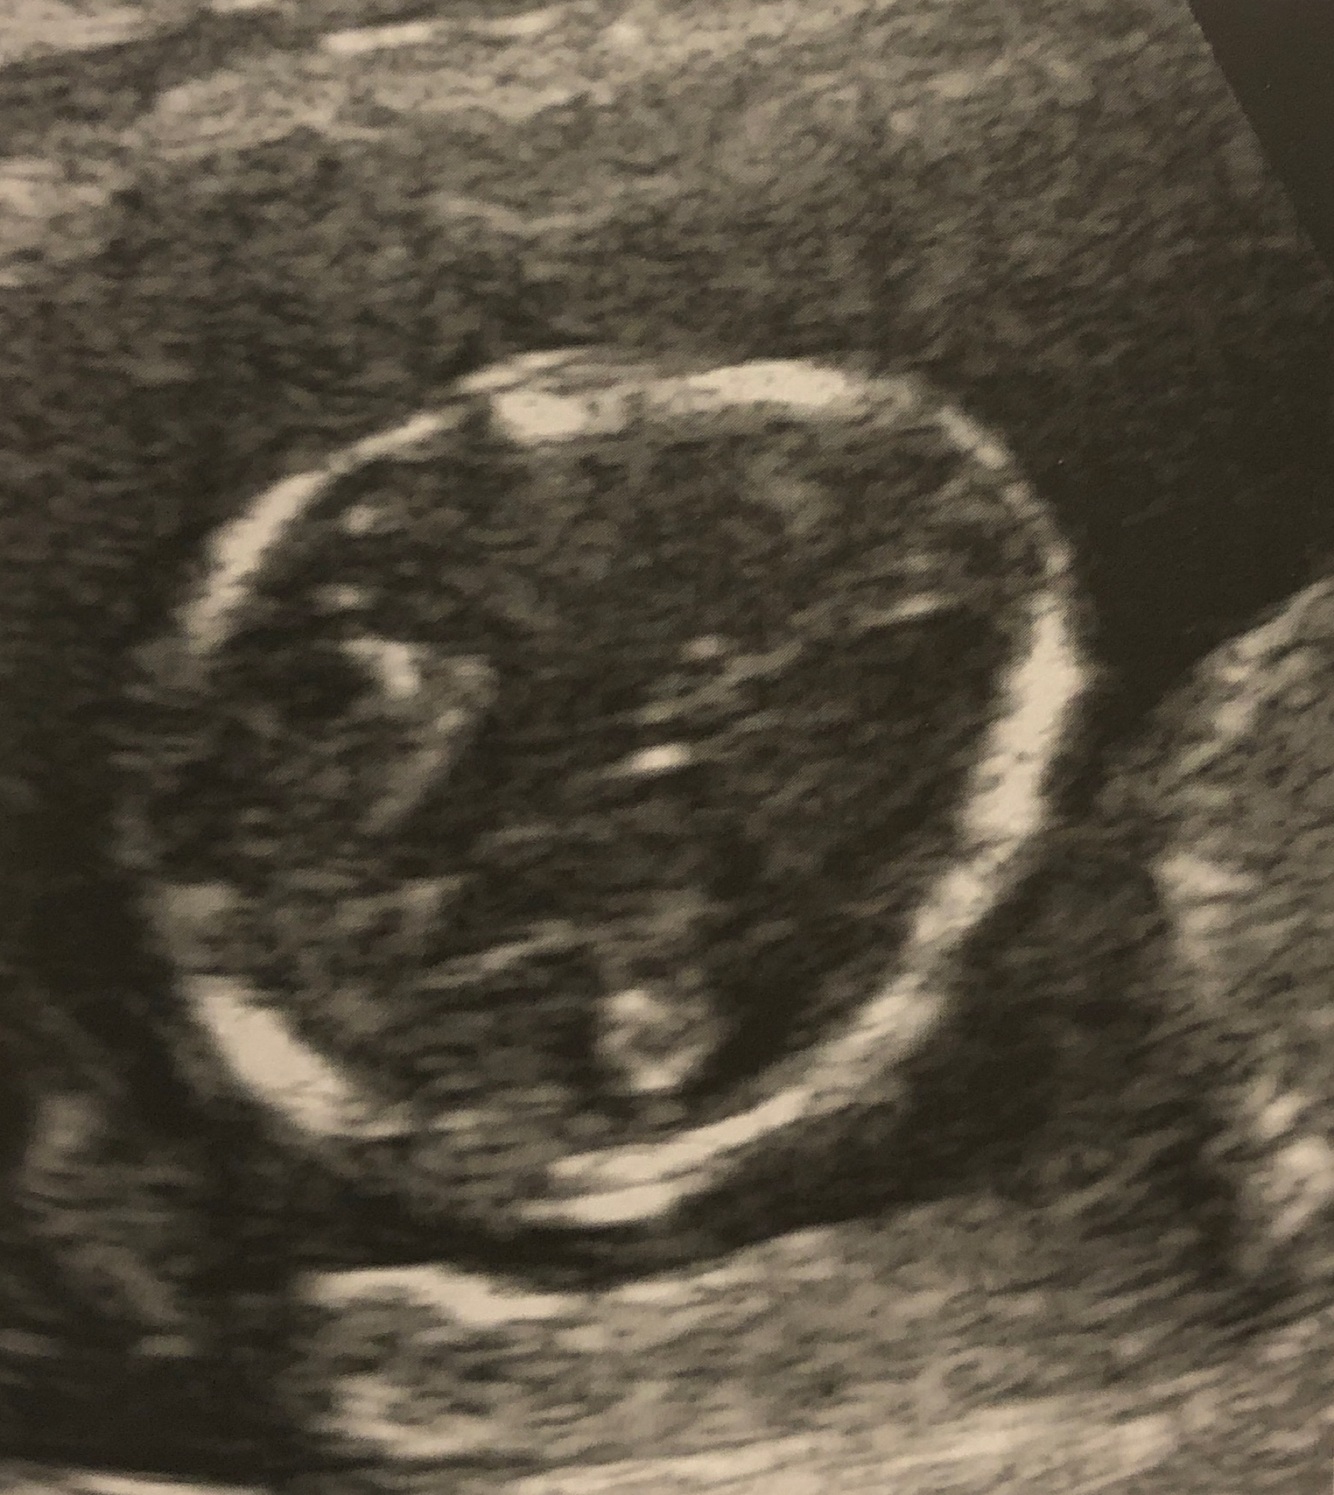

Q

What is this? Why abnormality is it associated with?

A

Strawberry shaped skull, trisomy 18/Edwards